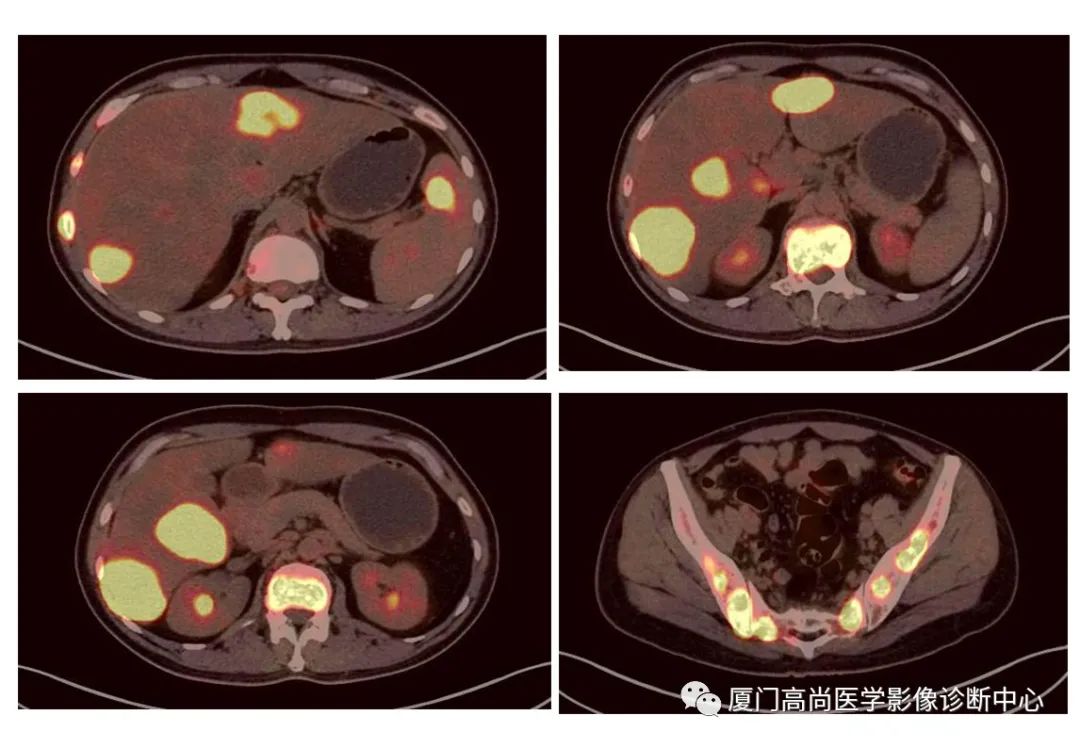

病例1:某男士,36歲,半年前摔傷,當(dāng)時無大礙,近幾個月來腰腿痛,并逐漸加重,消瘦10多斤。MRI檢查發(fā)現(xiàn)腰椎、骨盆 骨質(zhì)異常信號,查血各項腫瘤標(biāo)記物正常,因診斷不清而來做PET/CT檢查

淋巴瘤在骨骼、肝臟、脾臟、淋巴結(jié)表現(xiàn)

肝臟、脾臟、骨骼淋巴瘤病灶

骨骼、腋窩淋巴結(jié)病灶

PET/CT發(fā)現(xiàn) :全身多發(fā)淋巴結(jié)腫大,F(xiàn)DG攝取增高;肝臟、脾臟多發(fā)低密度結(jié)節(jié), FDG攝取增高;雙側(cè)扁桃體腫大,F(xiàn)DG攝取增高;全身多處骨骼破壞,F(xiàn)GD攝取增高;上述考慮為淋巴瘤

經(jīng)淋巴結(jié)穿刺活檢 :病理診斷為彌漫大B細(xì)胞淋巴瘤